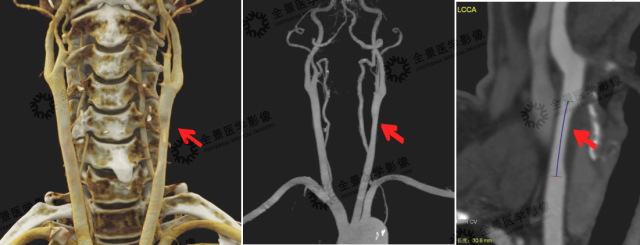

3. 头颈部 CTA

头颈部 VR 容积重建,可显示头颈部整体血管情况。MIP、MPR、CPR 等重建方式可清晰显示病变细节,如血管斑块的性质及稳定性、血管腔狭窄的位置、狭窄程度、有无血管变异、血栓或侧枝循环形成等情况;同时也可作为血管支架置入术后随访常用方式。

案例:左侧颈总动脉近分叉处见长节段斑块形成,病变长度约 30.6 mm,性质为软斑块(含脂质成分多,危险程度较高),管腔直径最重处接近中度狭窄(约 50%)。